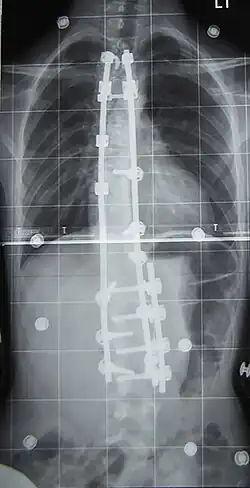

Surgery

Surgery is usually recommended by orthopedists for curves with a high likelihood of progression (i.e., greater than 45–50° of magnitude), curves that would be cosmetically unacceptable as an adult, curves in people with spina bifida and cerebral palsy that interfere with sitting and care, and curves that affect physiological functions such as breathing.[104][105]

Surgery is indicated by the Society on Scoliosis Orthopaedic and Rehabilitation Treatment (SOSORT) at 45–50°[4] and by the Scoliosis Research Society (SRS) at a Cobb angle of 45°.[106] SOSORT uses the 45–50° threshold as a result of the well-documented, plus or minus 5° measurement error that can occur while measuring Cobb angles.[106]

Surgeons who specialize in spine surgery perform surgery for scoliosis. To completely straighten a scoliotic spine is usually impossible, but for the most part, significant corrections are achieved.[107]

The two main types of surgery are:[108]

- Anterior fusion: This surgical approach is through an incision at the side of the chest wall.

- Posterior fusion: This surgical approach is through an incision on the back and uses metal instrumentation to correct the curve.

One or both of these surgical procedures may be needed. The surgery may be done in one or two stages and, on average, takes four to eight hours.

Surgery

In 1962, the American orthopaedic surgeon Paul Harrington introduced a metal spinal system of instrumentation that assisted with straightening the spine, as well as holding it rigid while fusion took place. The now obsolete Harrington rod operated on a ratchet system, attached by hooks to the spine at the top and bottom of the curvature that, when cranked, would distract—or straighten—the curve. The Harrington rod obviates the need for prolonged casting, allowing patients greater mobility in the postoperative period and significantly reducing the quality of life burden of fusion surgery. The Harrington rod was the precursor to most modern spinal instrumentation systems. A major shortcoming was that it failed to produce a posture wherein the skull would be in proper alignment with the pelvis, and it did not address rotational deformity. As the person aged, there would be increased wear and tear, early onset arthritis, disc degeneration, muscular stiffness, and acute pain. "Flatback" became the medical name for a related complication, especially for those who had lumbar scoliosis.[119]

In the 1960s, the gold standard for idiopathic scoliosis was a posterior approach using a single Harrington rod. Post-operative recovery involved bed rest, casts, and braces. Poor results became apparent over time.[120]

In the 1970s, an improved technique was developed using two rods and wires attached at each level of the spine. This segmented instrumentation system allowed patients to become mobile soon after surgery.[120]

In the 1980s, Cotrel–Dubousset instrumentation improved fixation and addressed sagittal imbalance and rotational defects unresolved by the Harrington rod system. This technique uses multiple hooks with rods to give stronger fixation in three dimensions, usually eliminating the need for postoperative bracing.[120]